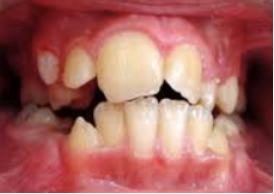

Supernumery Teeth

extra teeth

Most common form=Mesiodens

* occurs at midline of 8/9

* palatal position

migh block normal eruption of permanent teeth